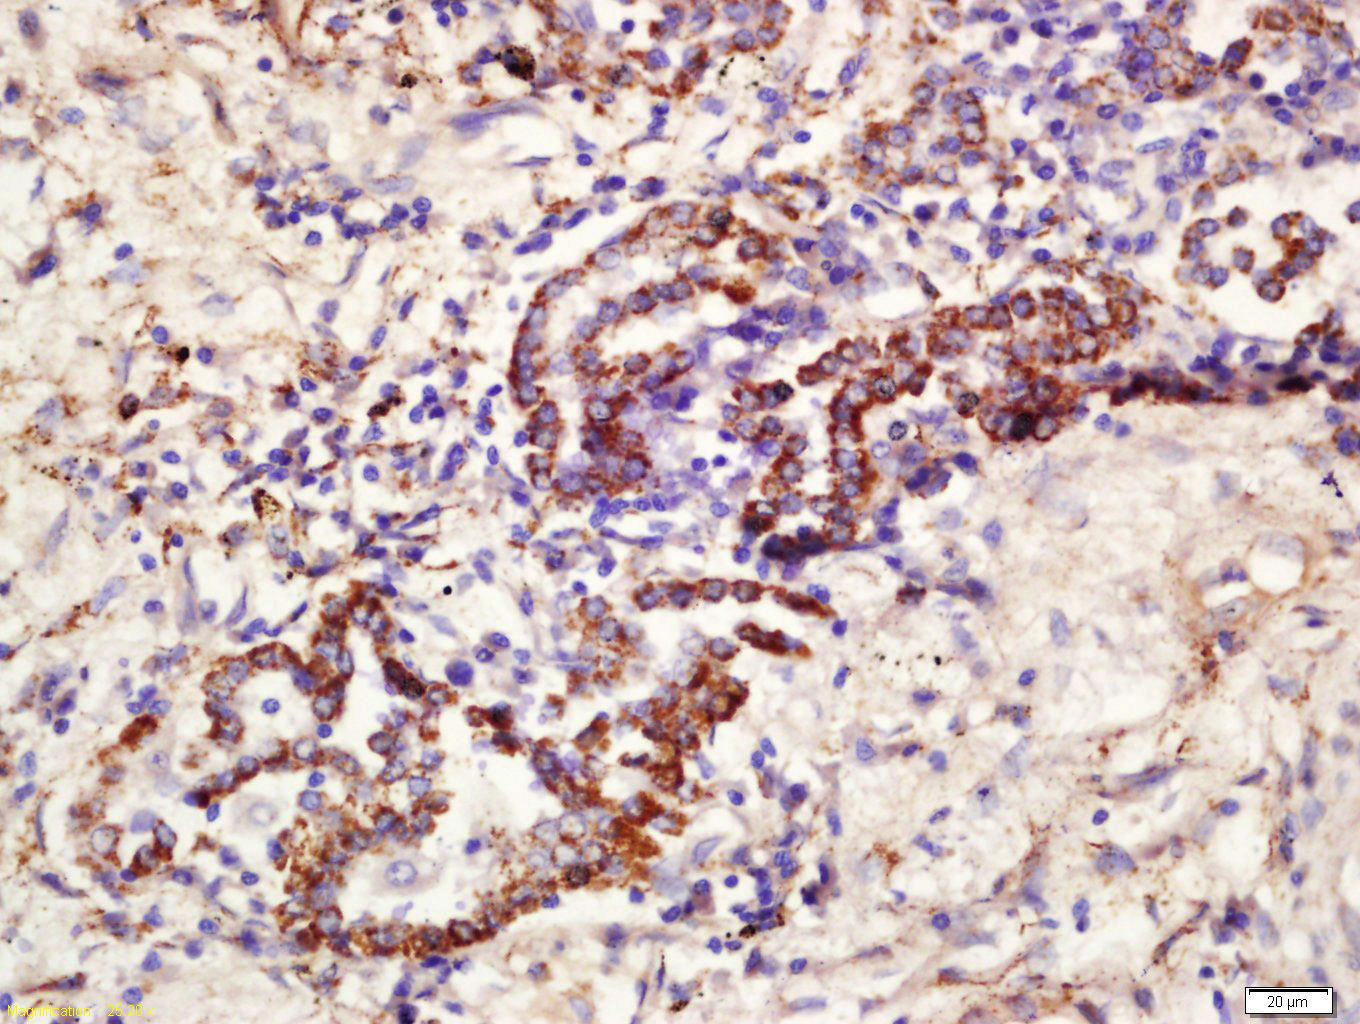

Tissue/cell: human lung carcinoma; 4% Paraformaldehyde-fixed and paraffin-embedded; Antigen retrieval: citrate buffer ( 0.01M, pH 6.0 ), Boiling bathing for 15min; Block endogenous peroxidase by 3% Hydrogen peroxide for 30min; Blocking buffer (normal goat serum,C-0005) at 37℃ for 20 min; Incubation: Anti-CD361 Polyclonal Antibody, Unconjugated(bs-14684R) 1:200, overnight at 4°C, followed by conjugation to the secondary antibody(SP-0023) and DAB(C-0010) staining